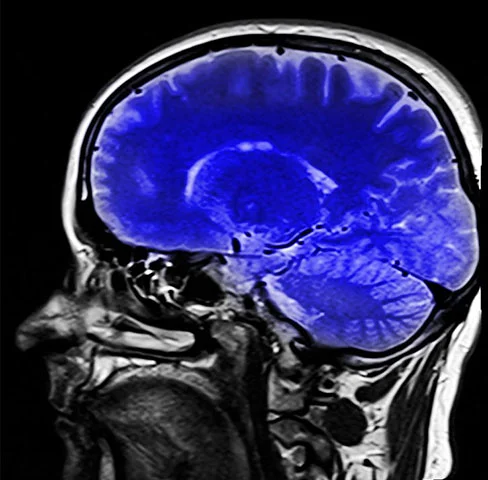

Saiba identificar os primeiros sinais de demência, doença que afeta Bruce Willis e Maurício Kubrusly